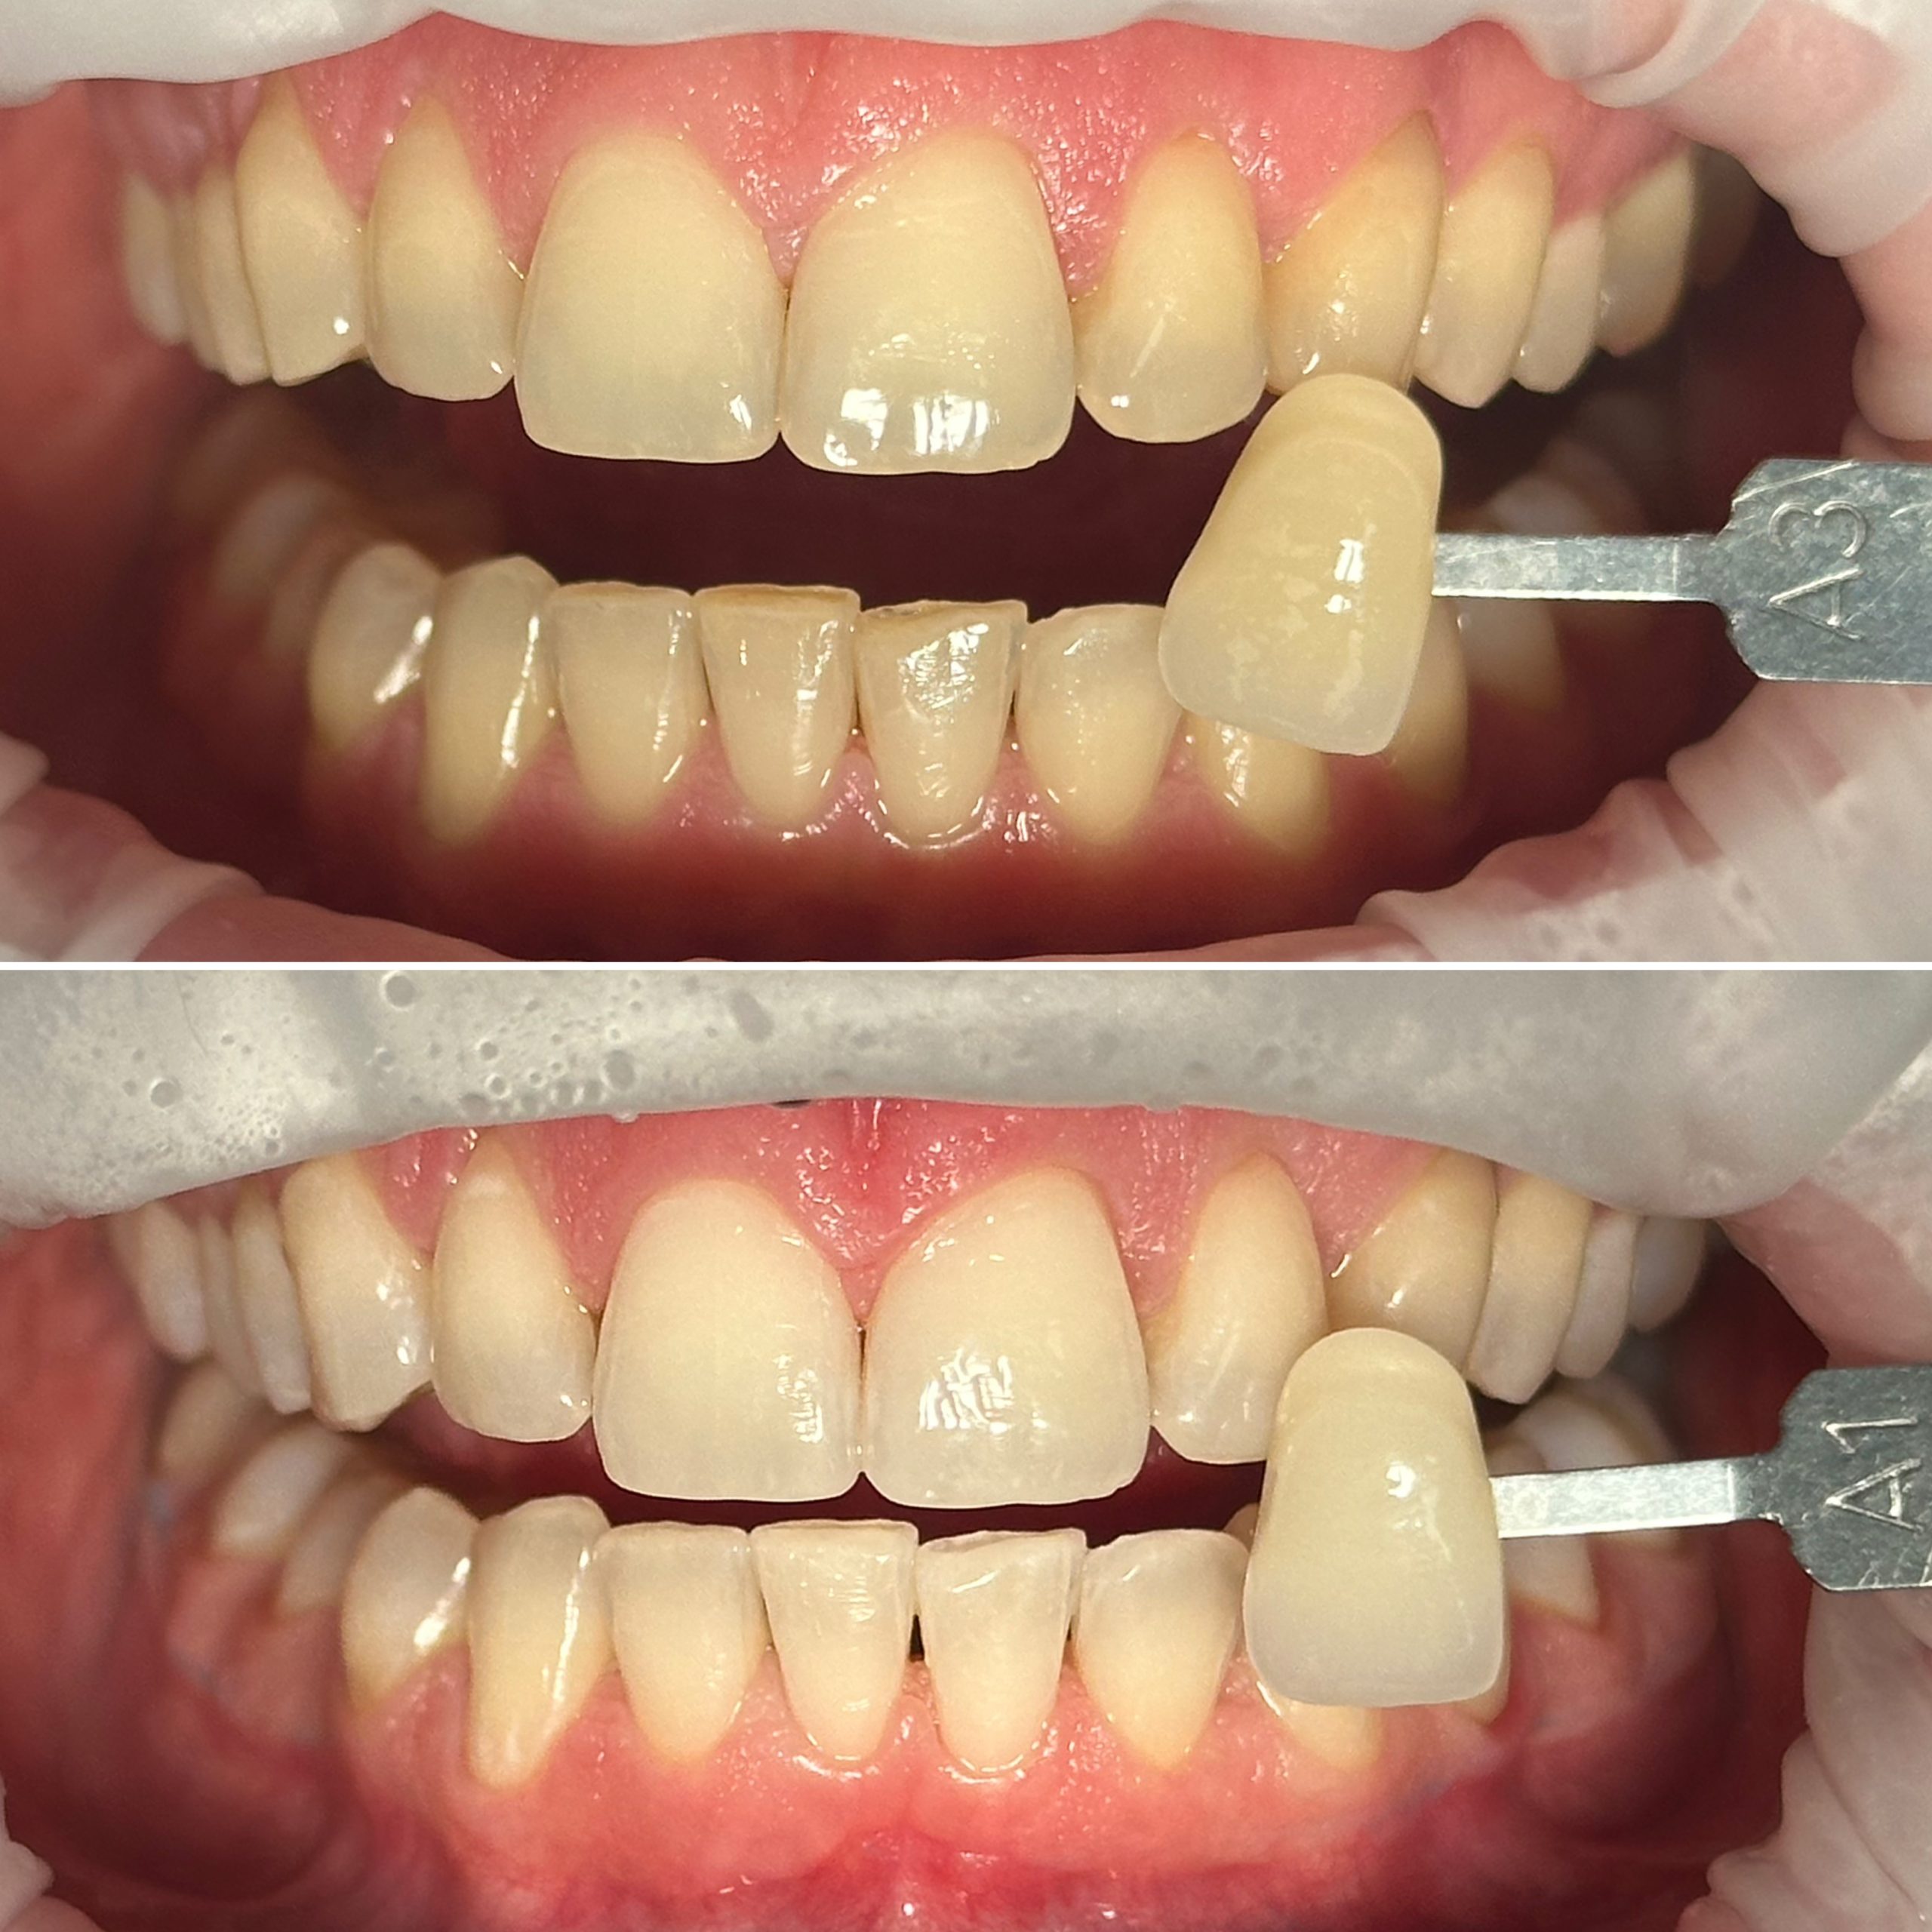

• Профессиональная отбелка зубов системой ZOOM,BEYOND

• Домашнее отбеливание зубов

2024 год – «Отбеливание от «А» до «Я» Александр Кирманов